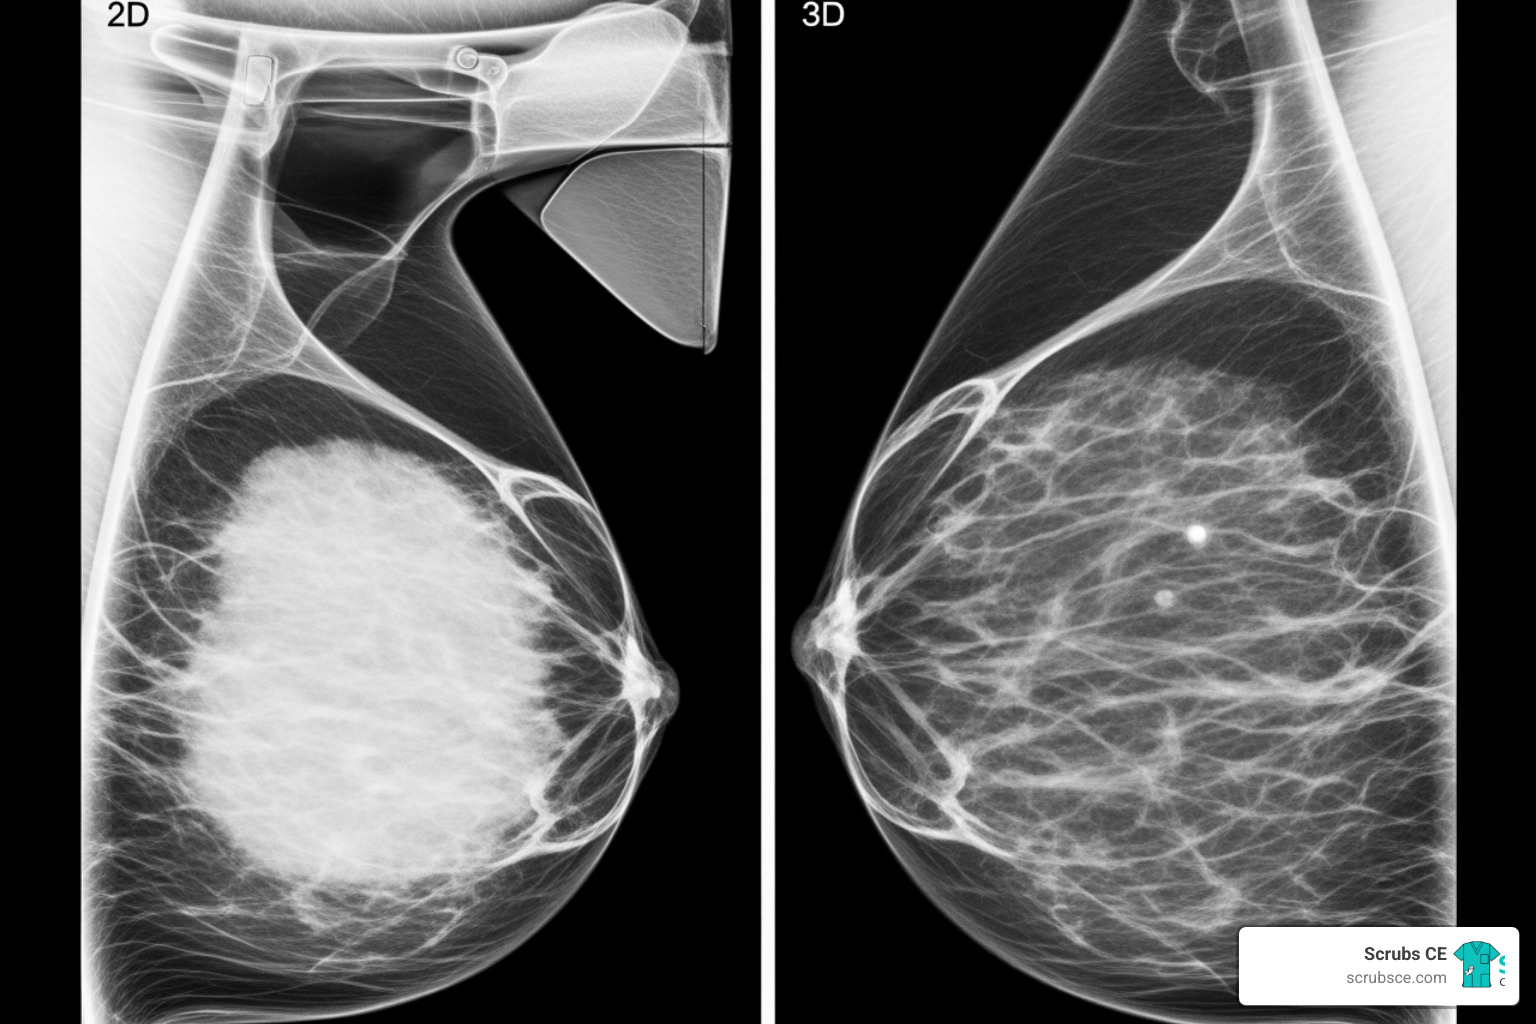

Digital breast tomosynthesis (DBT), or 3D mammography, overcomes the primary limitation of 2D mammography: tissue overlap.

How it works: The X-ray tube moves in an arc over the breast, capturing multiple low-dose images from different angles. A computer reconstructs these into a series of thin image “slices,” each about 1mm thick. Radiologists can scroll through these layers, effectively “seeing through” the breast tissue to spot abnormalities that might otherwise be hidden.

Benefits: DBT improves cancer detection for women of all breast densities and is particularly effective for finding invasive cancers in dense breasts. It also reduces callbacks by 15-40% compared to 2D mammography, meaning less anxiety and fewer unnecessary follow-up appointments for patients.